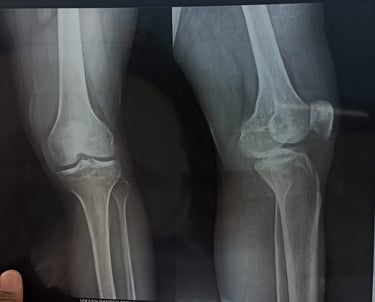

Rheumatic Relief

Gentle treatments easing joint stiffness and pain.